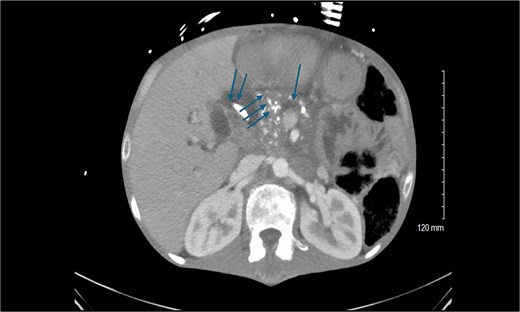

A 44-year-old man with a history of severe protein-calorie malnutrition (body mass index, 16), chronic hyponatremia, type 2 diabetes, and alcohol-induced chronic pancreatitis presented to our unit for surgical evaluation. Baseline laboratory findings included a total bilirubin of 4 mg/dl, a markedly elevated alkaline phosphatase level of 2848 IU/L, and clinical and biological evidence of severe malnutrition (Table 1). Abdominal computed tomography revealed common bile-duct dilatation (2.1 cm), scattered pancreatic parenchymal calcifications, main pancreatic duct dilatation (5 mm), duodenal strictures, and extensive peri-pancreatic inflammatory changes encasing the pancreatic head and superior mesenteric vein/portal vein, without vascular occlusion (Fig. 1). The biliary stricture had led to both intrahepatic and extrahepatic ductal dilatation. Endoscopic stenting was not feasible due to the duodenal stricture, necessitating insertion of a percutaneous transhepatic biliary drainage catheter.

Preoperative computed tomography scan of the abdomen showing the calcified head of the pancreas (triple arrows), dilated pancreatic duct (single arrow), and dilated common bile duct (double arrows).